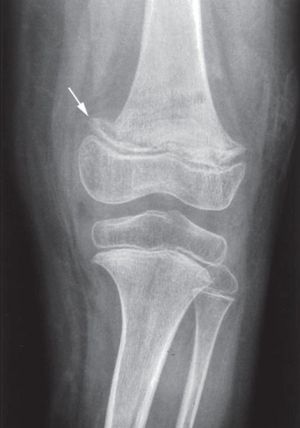

괴혈병 진단은 일반적으로 신체 징후, X-레이 검사 결과, 그리고 치료 후 증상이 호전되는지를 종합적으로 판단하여 이루어진다.[5]

괴혈병은 임상 증상이나 엑스레이 사진 소견이 다른 여러 소아 질환과 유사할 수 있어 감별 진단이 중요하다. 감별해야 할 주요 질환은 다음과 같다.